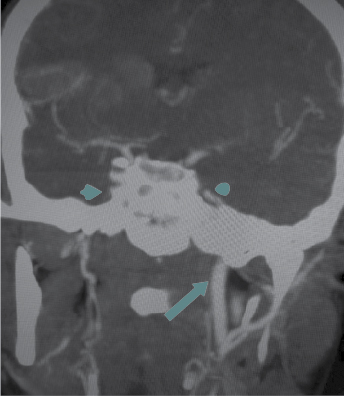

Arterial Doppler of upper limbs showed significant stenosis in the proximal subclavian artery. CT angiogram of brain (Fig. 3) and chest (Fig. 4) showed complete occlusion of right common carotid artery and 50% occlusion of left common carotid, 20% to 30% luminal narrowing of both internal and external carotid artery, occlusion of left and right vertebral artery, both subclavian artery occlusion (30% occlusion), both axillary, brachial, radial, ulnar artery and descending thoracic aorta (20% occlusion). Renal arteries, abdominal aorta, external and internal iliac arteries on both sides were normal.

Figure 3. CT angiography of brain – Nonvisualization of infraclinoid part of right internal carotid artery, nonvisualization of right common carotid artery.